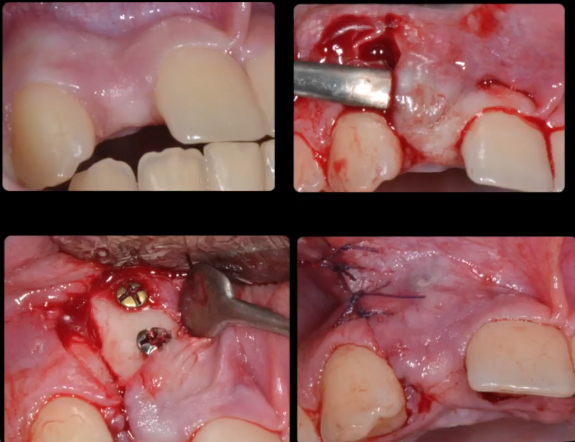

The management of the anterior open bite may be quite challenging and in some cases necessitates a multidisciplinary approach. We present here a patient suffering from an anterior open bite with an ankylosed central incisor due to previous trauma. The anterior open bite was corrected using conventional orthodontics and the ankylosed incisor was repositioned in the correct tri dimensional position using segmental osteotomy. The repositioned bone block needed 5 months of stabilization and the prosthetic rehabilitation of the anterior maxilla was completed using e-max crowns. At 24 months ,the result was stable with no relapse and an excellent pink and white esthetic score.